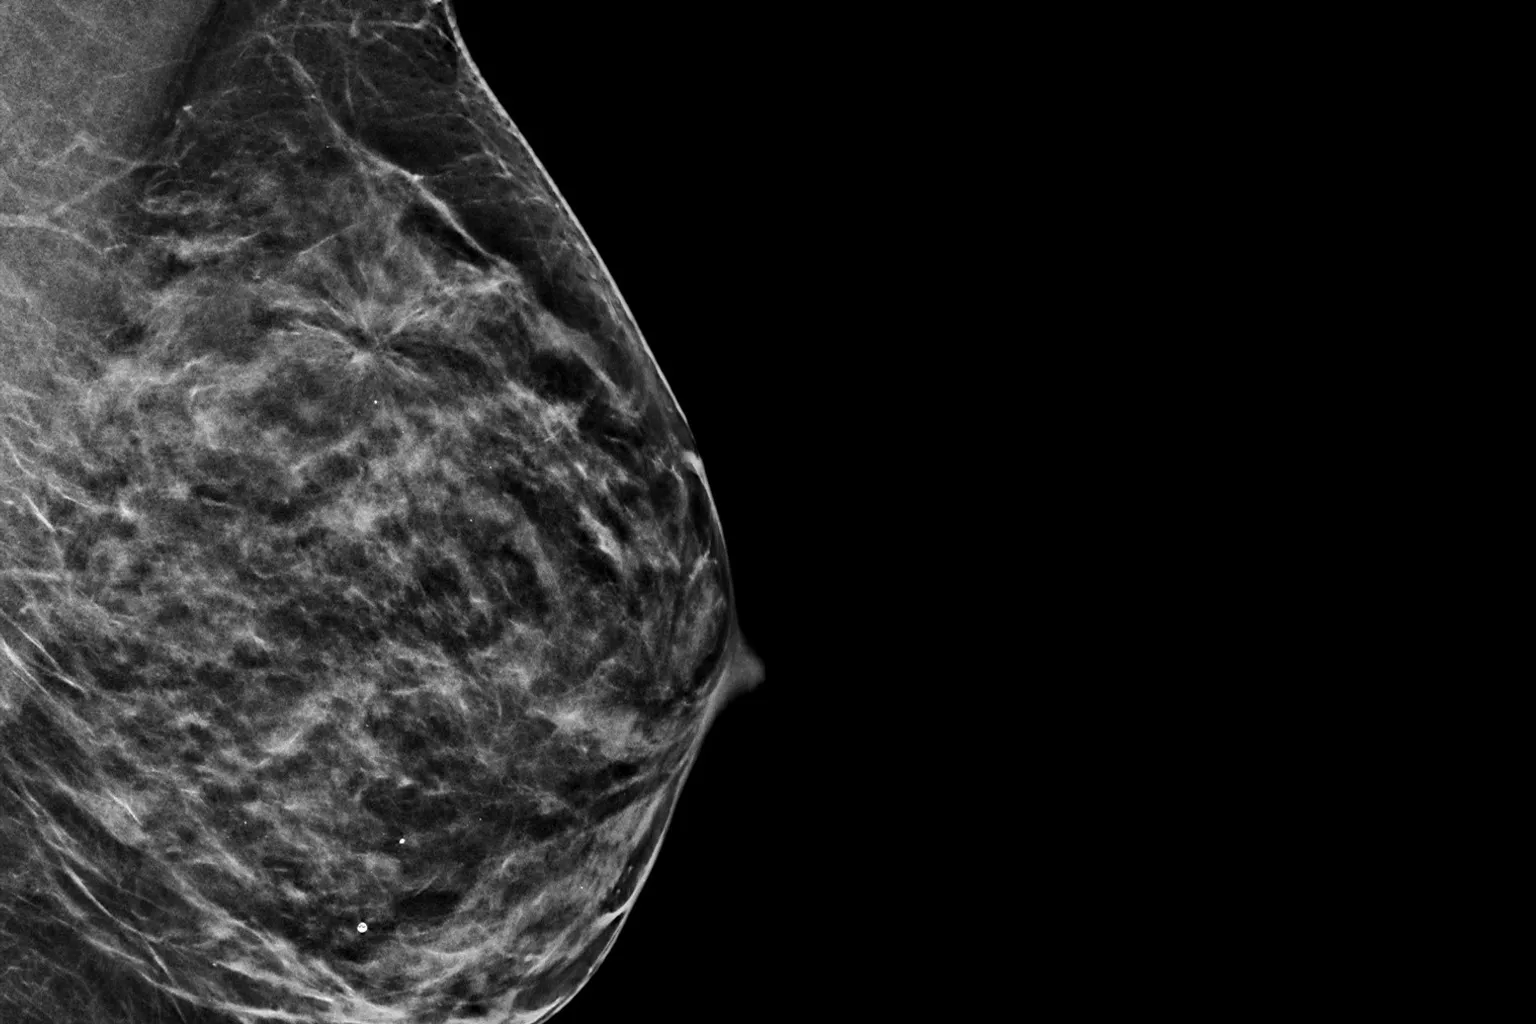

Imagens de vários raio-X mamários